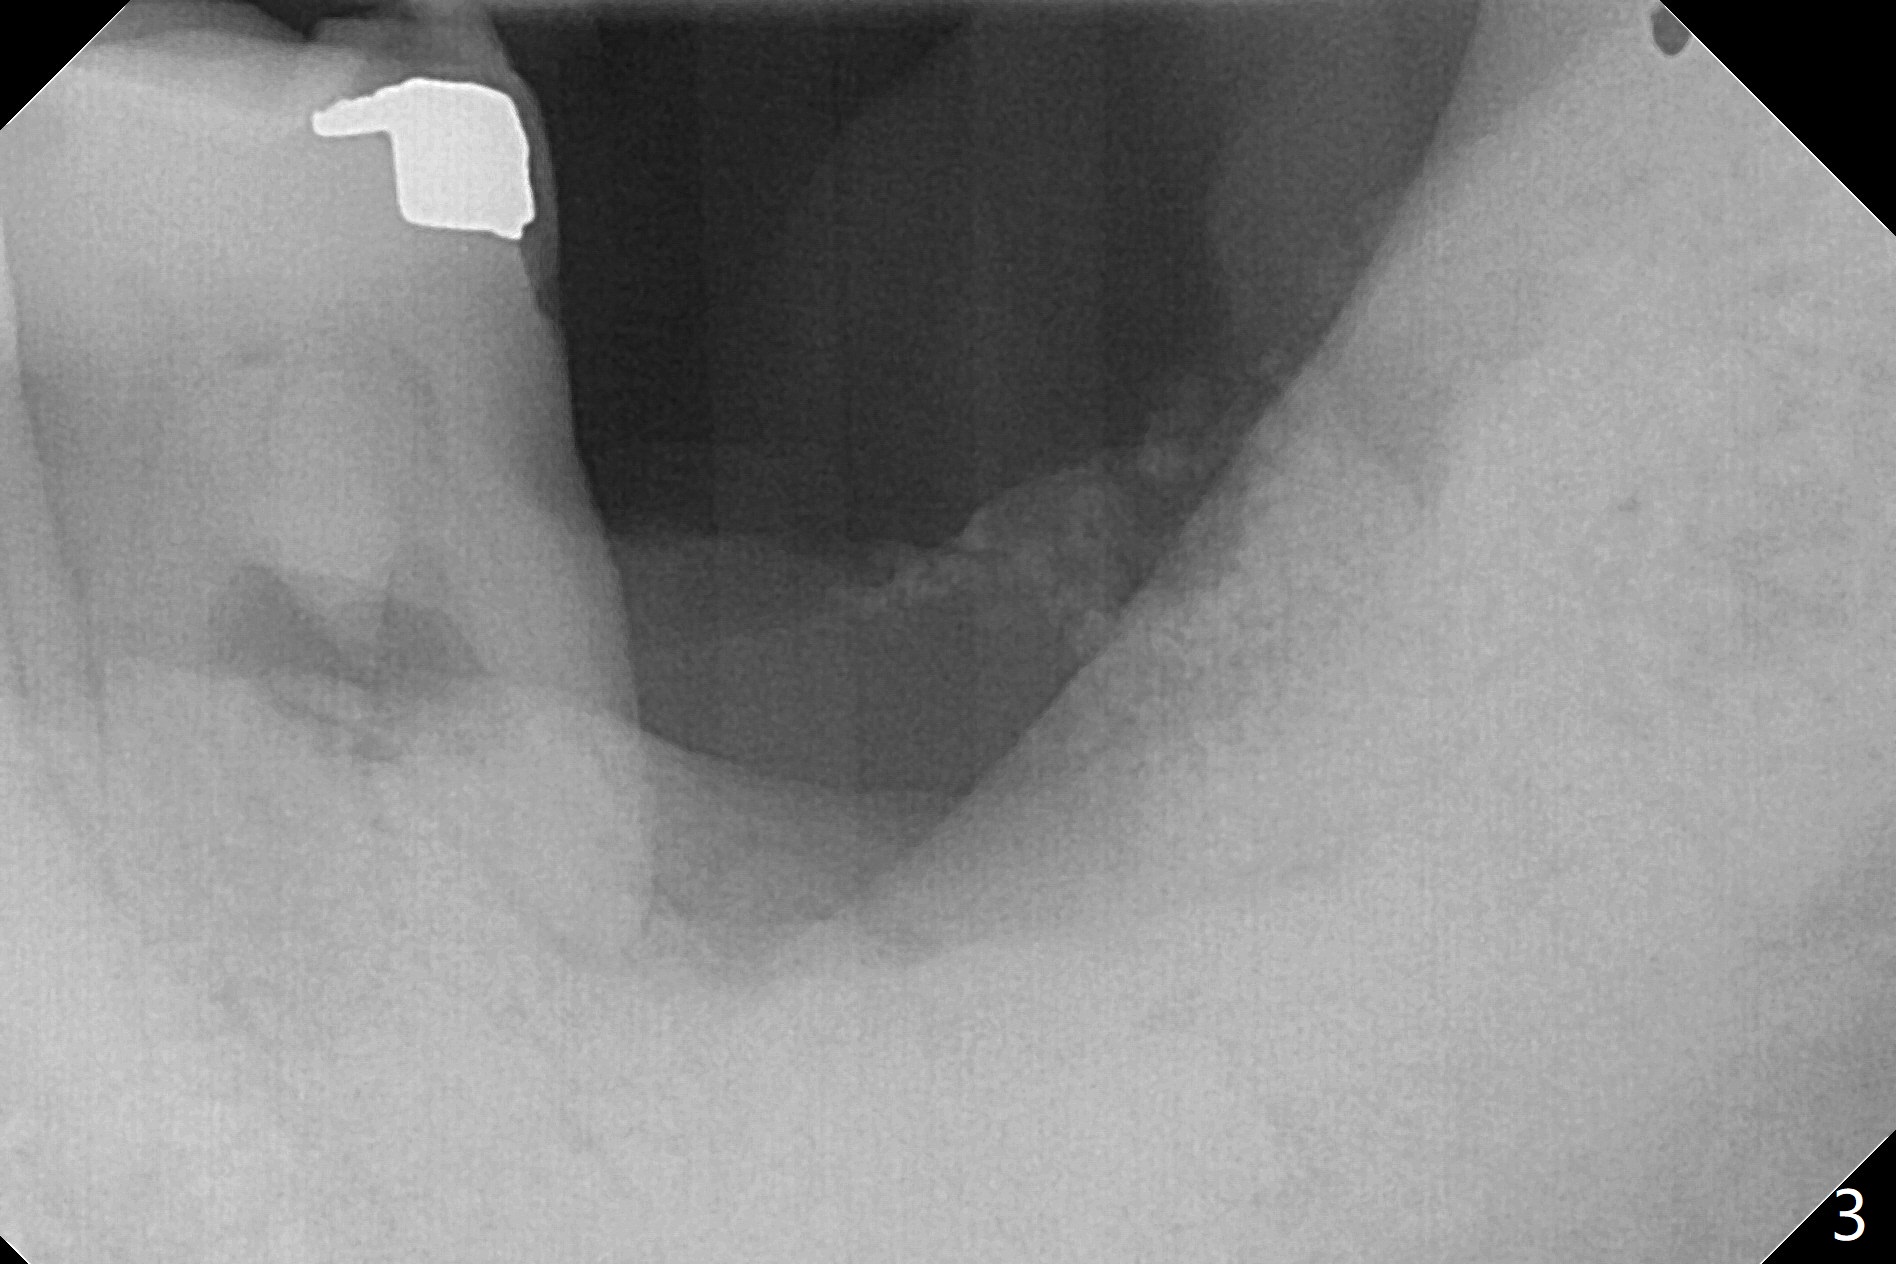

50岁男两年前不肯拔除左下7(图一),现在主动要求治疗(图二),需要做位点保留?怎么做的好?怎么收拾不动脑筋的惨剧(图三:仅远中牙槽窝植骨)?其实需要掀开近中粘骨膜(图四:箭头),然后植骨(红圆圈)。术后4.5个月近中缺损(图五:*),需要植牙植入很低(图六),离邻牙CEJ(<)很远。因此植体应该植入浅些(图七(CT矢状切面):箭头),离牙龈3毫米。放置袖3毫米(图八:粉红色)基台(紫色),然后在基台和植牙浅部植入粘性骨粉(图九:红圆圈)以及PRF膜(蓝线)。从冠状切面来看,颊侧(图十:B)需要多植骨,植牙前翻瓣(图十一:箭头),放置基台后(图十二),放置骨粉,膜,缝合。No Deviation 14 手术 Xin Wei, DDS, PhD, MS 1st edition 09/22/2020, last revision 03/02/2021